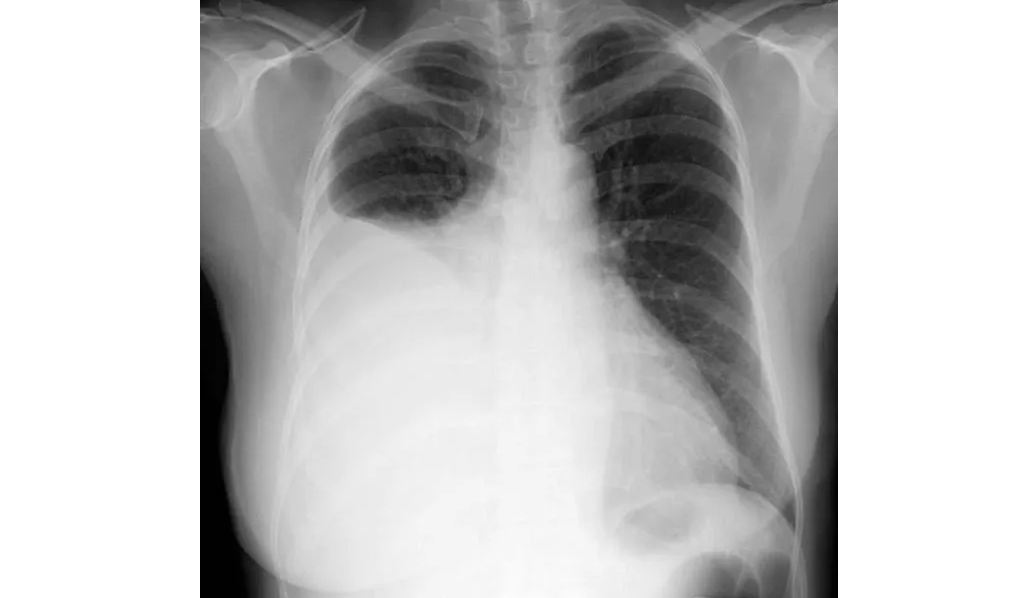

La neumonía adquirida en la comunidad es común y puede provocar sepsis, síndrome de dificultad respiratoria aguda o muerte. El tratamiento de primera línea varía según la gravedad y la etiología de la enfermedad. Los pacientes hospitalizados con sospecha de NAC bacteriana y sin factores de riesgo de bacterias resistentes pueden ser tratados con una terapia combinada de β-lactámicos/macrólidos, como ceftriaxona combinada con azitromicina, durante un mínimo de 3 días. JAMA, 16 de septiembre de 2024.